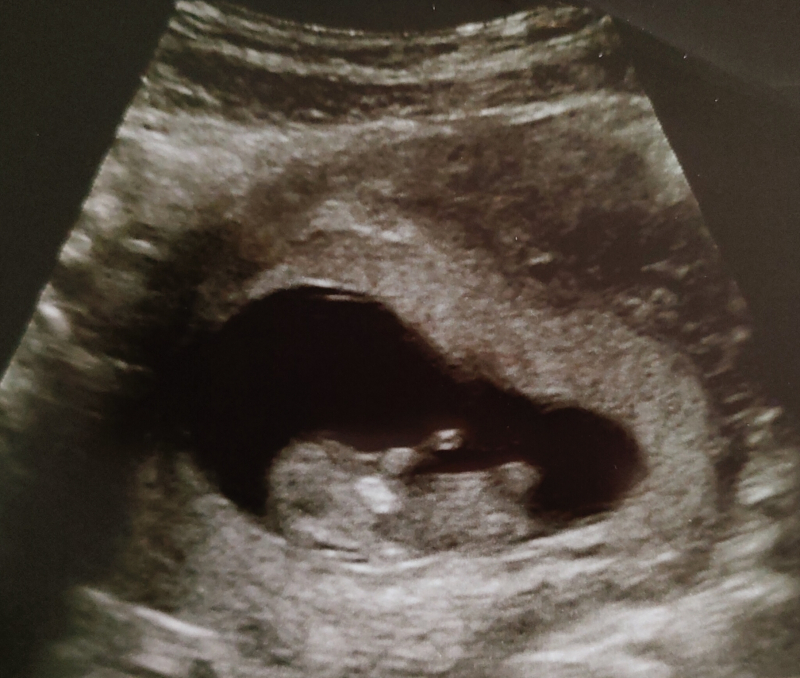

9週5日目のエコー写真です。

赤ちゃんの顎?首?周りの白い丸の様な物が気になります。

何か分かりますでしょうか?

顎の付近ということですと、少し白く濃く見えるところのことでしょうか?実際にエコーを拝見していませんので、はっきりとは明言できませんが、エコーは超音波をお腹に当てて、その反応によって画像を写していますので、エコーを当てる角度やお子さんの位置などによって、ある部分が濃く見えたり、影のように見えることもあります。お写真からですと、はっきりとしたことが分からず、申し訳ありませんが、もし気になるようであれば、次回の健診時に担当医にご確認なさってみてくださいね。